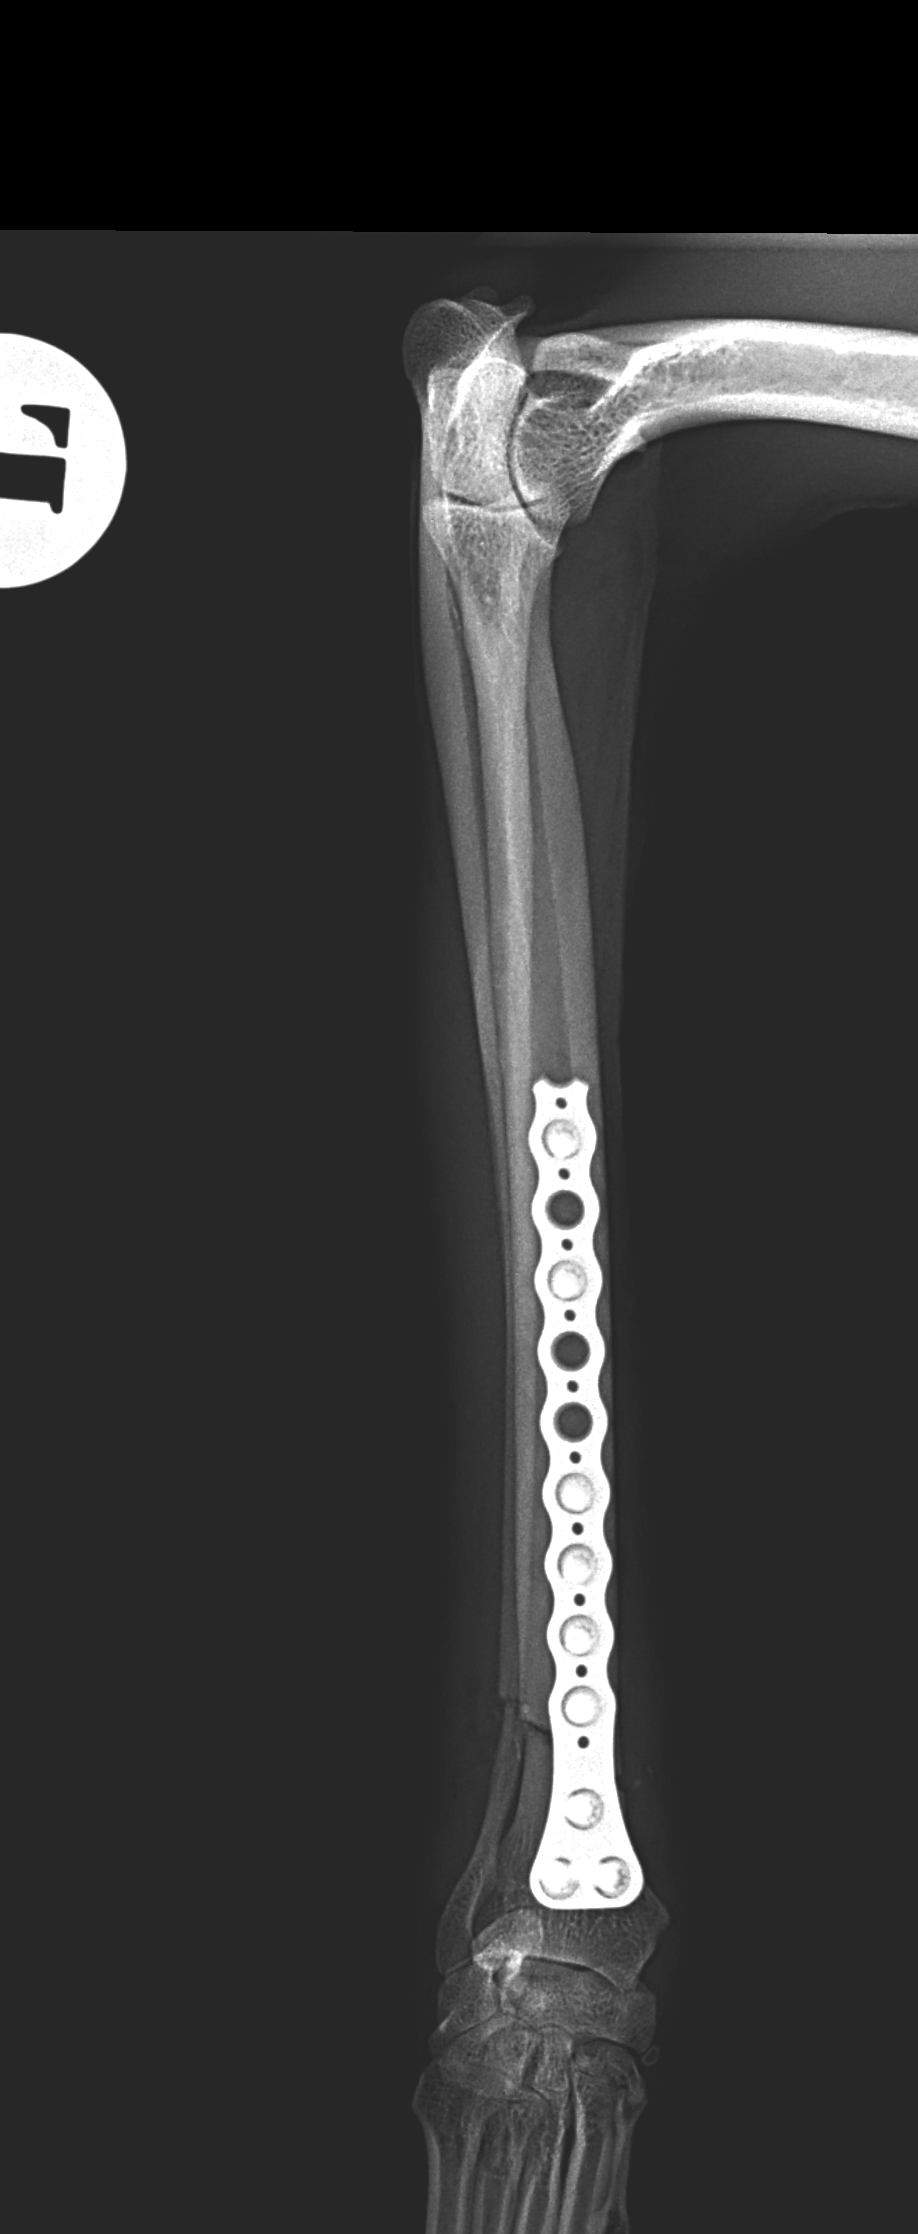

橈骨固定術 #239

イタリアングレーハウンドがジャンプした後から跛行しているとの事。2.4 Locking Plateで固定術を行いました。しばらくはインプラントにロードベアリングしているため骨がロードシェアできるまでは初期固定強度を担保するために外固定の併用を行います。